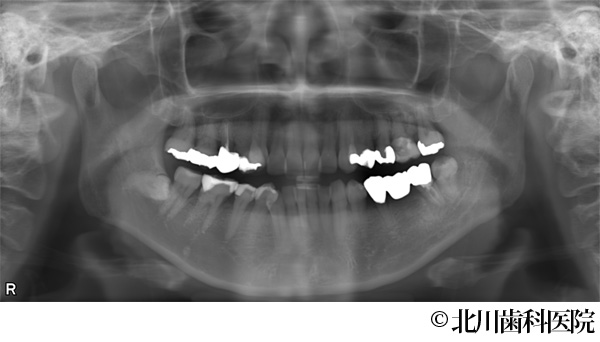

【症例1】インプラントと自家歯牙移植にて機能回復を行った症例

- 治療前

- インプラントと自家歯牙移植にて機能回復を行った症例

- 737,000円(税込)

- 1年3ヵ月

- 女性・50代

左下の奥歯が腫れて痛みがあり、抜歯後にインプラントを希望されて来院されました。

左下の奥歯は2本分の歯を喪失することになるため、抜歯する予定の歯の一つ手前にインプラントを埋め込み、抜歯部には親知らずを移植しクラウン(被せ物)を装着することで対応しました。

インプラントと移植歯により喪失した歯を補うことができ、審美面・機能面の回復につながりました。また、インプラント埋入と同時に移植を行うことで手術が一度に終わり身体の負担を軽減して行うことができました。